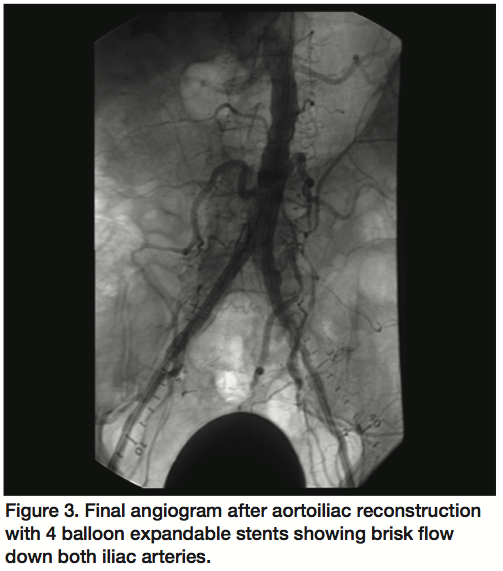

A 72-year-old male with a 5-year history of lifestyle limiting bilateral lower extremity claudication was evaluated by peripheral angiogram. Right femoral angiogram revealed total occlusion of the right common iliac artery (CIA). Left femoral angiogram revealed total occlusion of the left CIA. The length of occlusion was noted to be 5 cm on the right and 10 cm on the left. Subsequent aortogram from left brachial artery access confirmed complete occlusion of the distal abdominal aorta with collaterals filling both iliac arteries (Figure 1). A Wildcat CTO device (Avinger, Redwood City, California) was advanced retrograde through the right CIA occlusion to successfully cross into the distal abdominal aorta with intraluminal position confirmed by contrast injection. Balloon angioplasty was performed within the right CIA with an Evercross 8 x 80 mm balloon (ev3 Inc., Plymouth, Minnesota) with modest improvement of stenosis and significant vessel recoil. The Wildcat device (Avinger) was then advanced retrograde through the left CIA occlusion but entered a subintimal dissection plane. After multiple unsuccessful attempts with wires and support catheters to cross into the true lumen, an Outback Re-entry device (Cordis Endovascular, Warren, New Jersey) was used to attempt re-entry. Due to significant distal aortic disease and vessel recoil, the puncture needle and wire were unable to re-enter the true lumen. The Evercross 8 x 80 mm inflated balloon (ev3 Inc.) was then positioned in the distal aorta as a target for the Outback catheter (Cordis) (Figure 2) while the needle was advanced to puncture the balloon. The wire was then advanced into the abdominal aorta with intraluminal position confirmation with contrast injection. Bilateral CIA simultaneous kissing balloon angioplasty was then performed without complication, with reconstruction of the aortoiliac bifurcation using a total of 4 balloon expandable covered stents. Final angiogram showed a patent abdominal aorta and bilateral CIA with brisk flow down both lower extremities (Figure 3).

Re-entry devices have transformed the world of endovascular medicine and supported the successful revascularization of PAD, a condition that was once only operable. The Outback re-entry device uses angiographic guidance to position a puncture needle to enter the true lumen and advance a wire to make stent-supported angioplasty feasible.1,2 True lumen re-entry is highly successful, 87% in femoropopliteal and 91% in aortoiliac occlusions, as demonstrated in a single-center study.3 Factors such as vessel position, tortuosity, severe calcification, and plaque burden often make re-entry challenging. We present a case with an innovative approach to facilitating re-entry, using an inflated balloon as a “target” for needle puncture and wire entry when conventional re-entry is unsuccessful. This technique allows for 3-dimensional visualization of the target lumen while stabilizing the vascular structure without movement, which likely improves success of re-entry. In complex anatomical situations, this method may offer incremental benefit and success in revascularization.